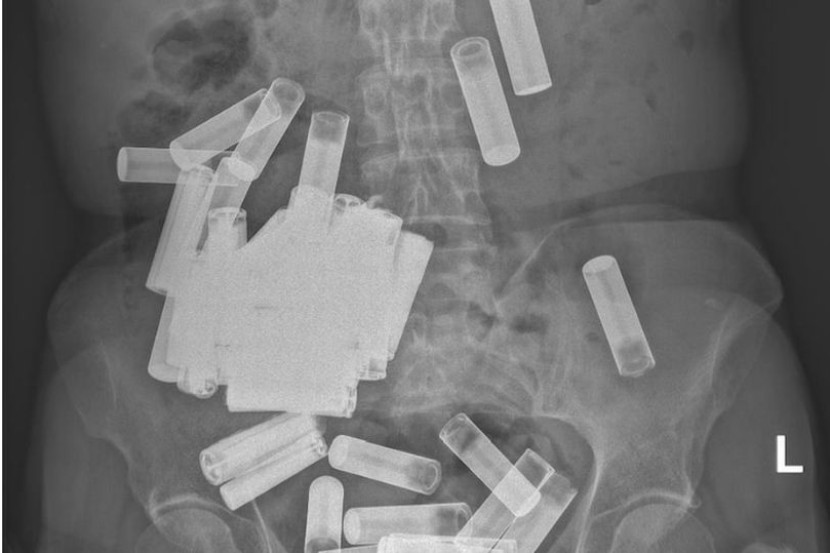

Sebanyak 55 bateri ditemui di dalam badan seorang pesakit wanita berusia 66 tahun.

Penemuan itu dibuat selepas imbasan X-ray mengesan objek asing di dalam badannya.

Sebanyak 46 bateri dikeluarkan melalui pembedahan. foto Irish Medical Journal

Menurut laporan dalam Jurnal Perubatan Ireland, wanita itu berjaya mengeluarkan lima bateri AA pada minggu pertama, tetapi selebihnya tersekat.

Susulan itu, pakar bedah mengeluarkan 46 daripada baki bateri, sekali gus menyaksikan empat biji masih terperangkap dalam saluran ususnya.

Ini menjadikan jumlah keseluruhan bateri yang dia termakan kepada adalah 55 bateri AA dan AAA.